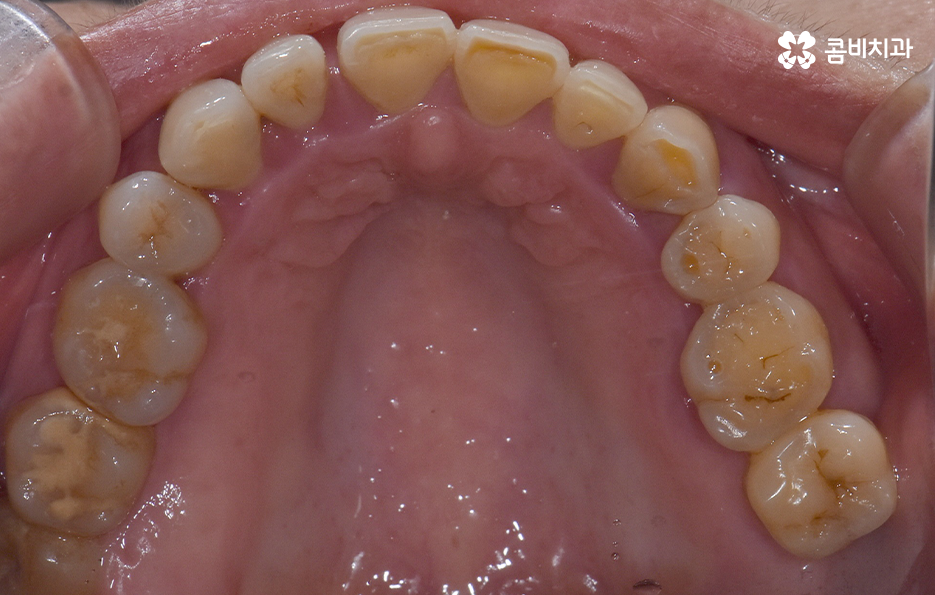

오늘 보시는 포스팅에서의 치료 과정도 어금니에 임플란트가 필요한 상태에서 윗니를 보시면 윗니가 다소 벌어진 것을 확인할 수 있는데요. 교정 하면 보통 전체교정을 떠올리게 되긴 하지만 경우에 따라서는 치열이 전체적으로 가지런한 편인데 앞니가 살짝 벌어진 경우나 어금니만 다소 벌어진 경우도 있을 거예요

이러한 경우에는 부분교정을 통해서 다소 개선이 필요한 치열을 가지런하게 만들고 가지런해진 치열과 교합 상태에 적합한 임플란트 치료 계획을 세워서 치아의 심미성과 기능적인 부분, 얼굴과의 조화를 종합적으로 고려하여 좋은 결과를 얻을 수 있어요